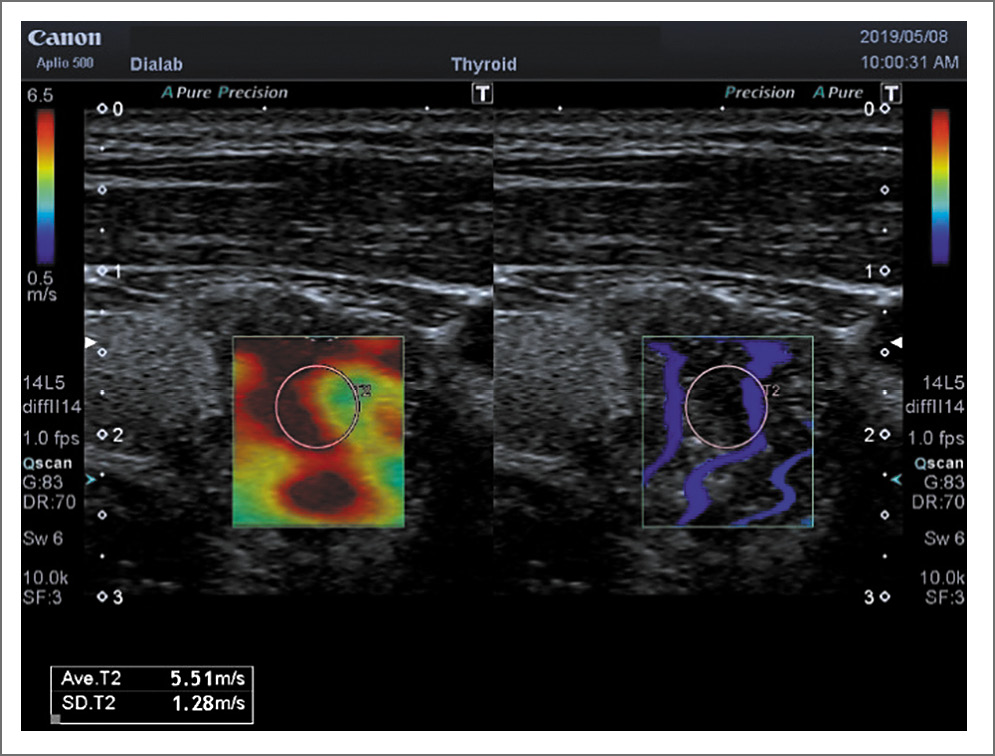

Рис. 6. ПР на фоне АИТ. Shear Wave – 96,2 кПа

Наши данные относительно показателей жесткости неизменной паренхимы ЩЖ в контрольной группе практически совпадают с данными литературы. Так, по данным А.Н. Катрич и соавт. [28], значение модуля Юнга составило 13,75 кПа, В.В. Митькова и соавт. [29] – 12,5 кПа, по данным В.С. Паршина и соавт. [30] – 15,60 кПа. Значение модуля Юнга в злокачественных образованиях ЩЖ по данным А.Н. Катрич и соавт. [28] составило 48,78 кПа (13,67–60,0 кПа), по результатам наших исследований – несколько выше – 67,0±1,9 кПА (135,0; 34,0 кПА); рис. 7, 8.

Рис. 8. ПР на фоне АИТ. Shear Wave – 5,51 м/с

Необходимо отметить, что в нашей работе при проведении эластографии сдвиговой волной измерение модуля Юнга проводилось также в м/с. При этом получены такие же закономерности, как и при измерении в кПа (см. табл. 2). Однако в большинстве работ измерения проведены в кПа, в связи с чем и обсуждались показатели именно в этих единицах.